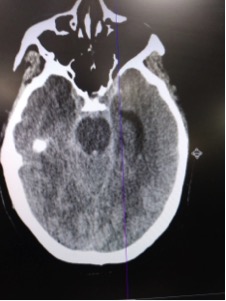

Patient was rushed to CT given clinical hx and presentation.

CT read as large amount of subarachnoid hemorrhage, suspicious for ruptured aneurysm.